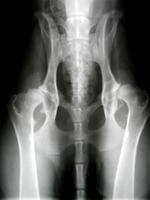

如果你注意到寶寶出現以上任何問題,要及時帶他去醫院檢查。醫生不僅通過體格檢查來診斷髖關節發育不良,還可能會藉助B超、X光來觀察髖關節的發育情況,以便儘早發現寶寶是否存在問題。